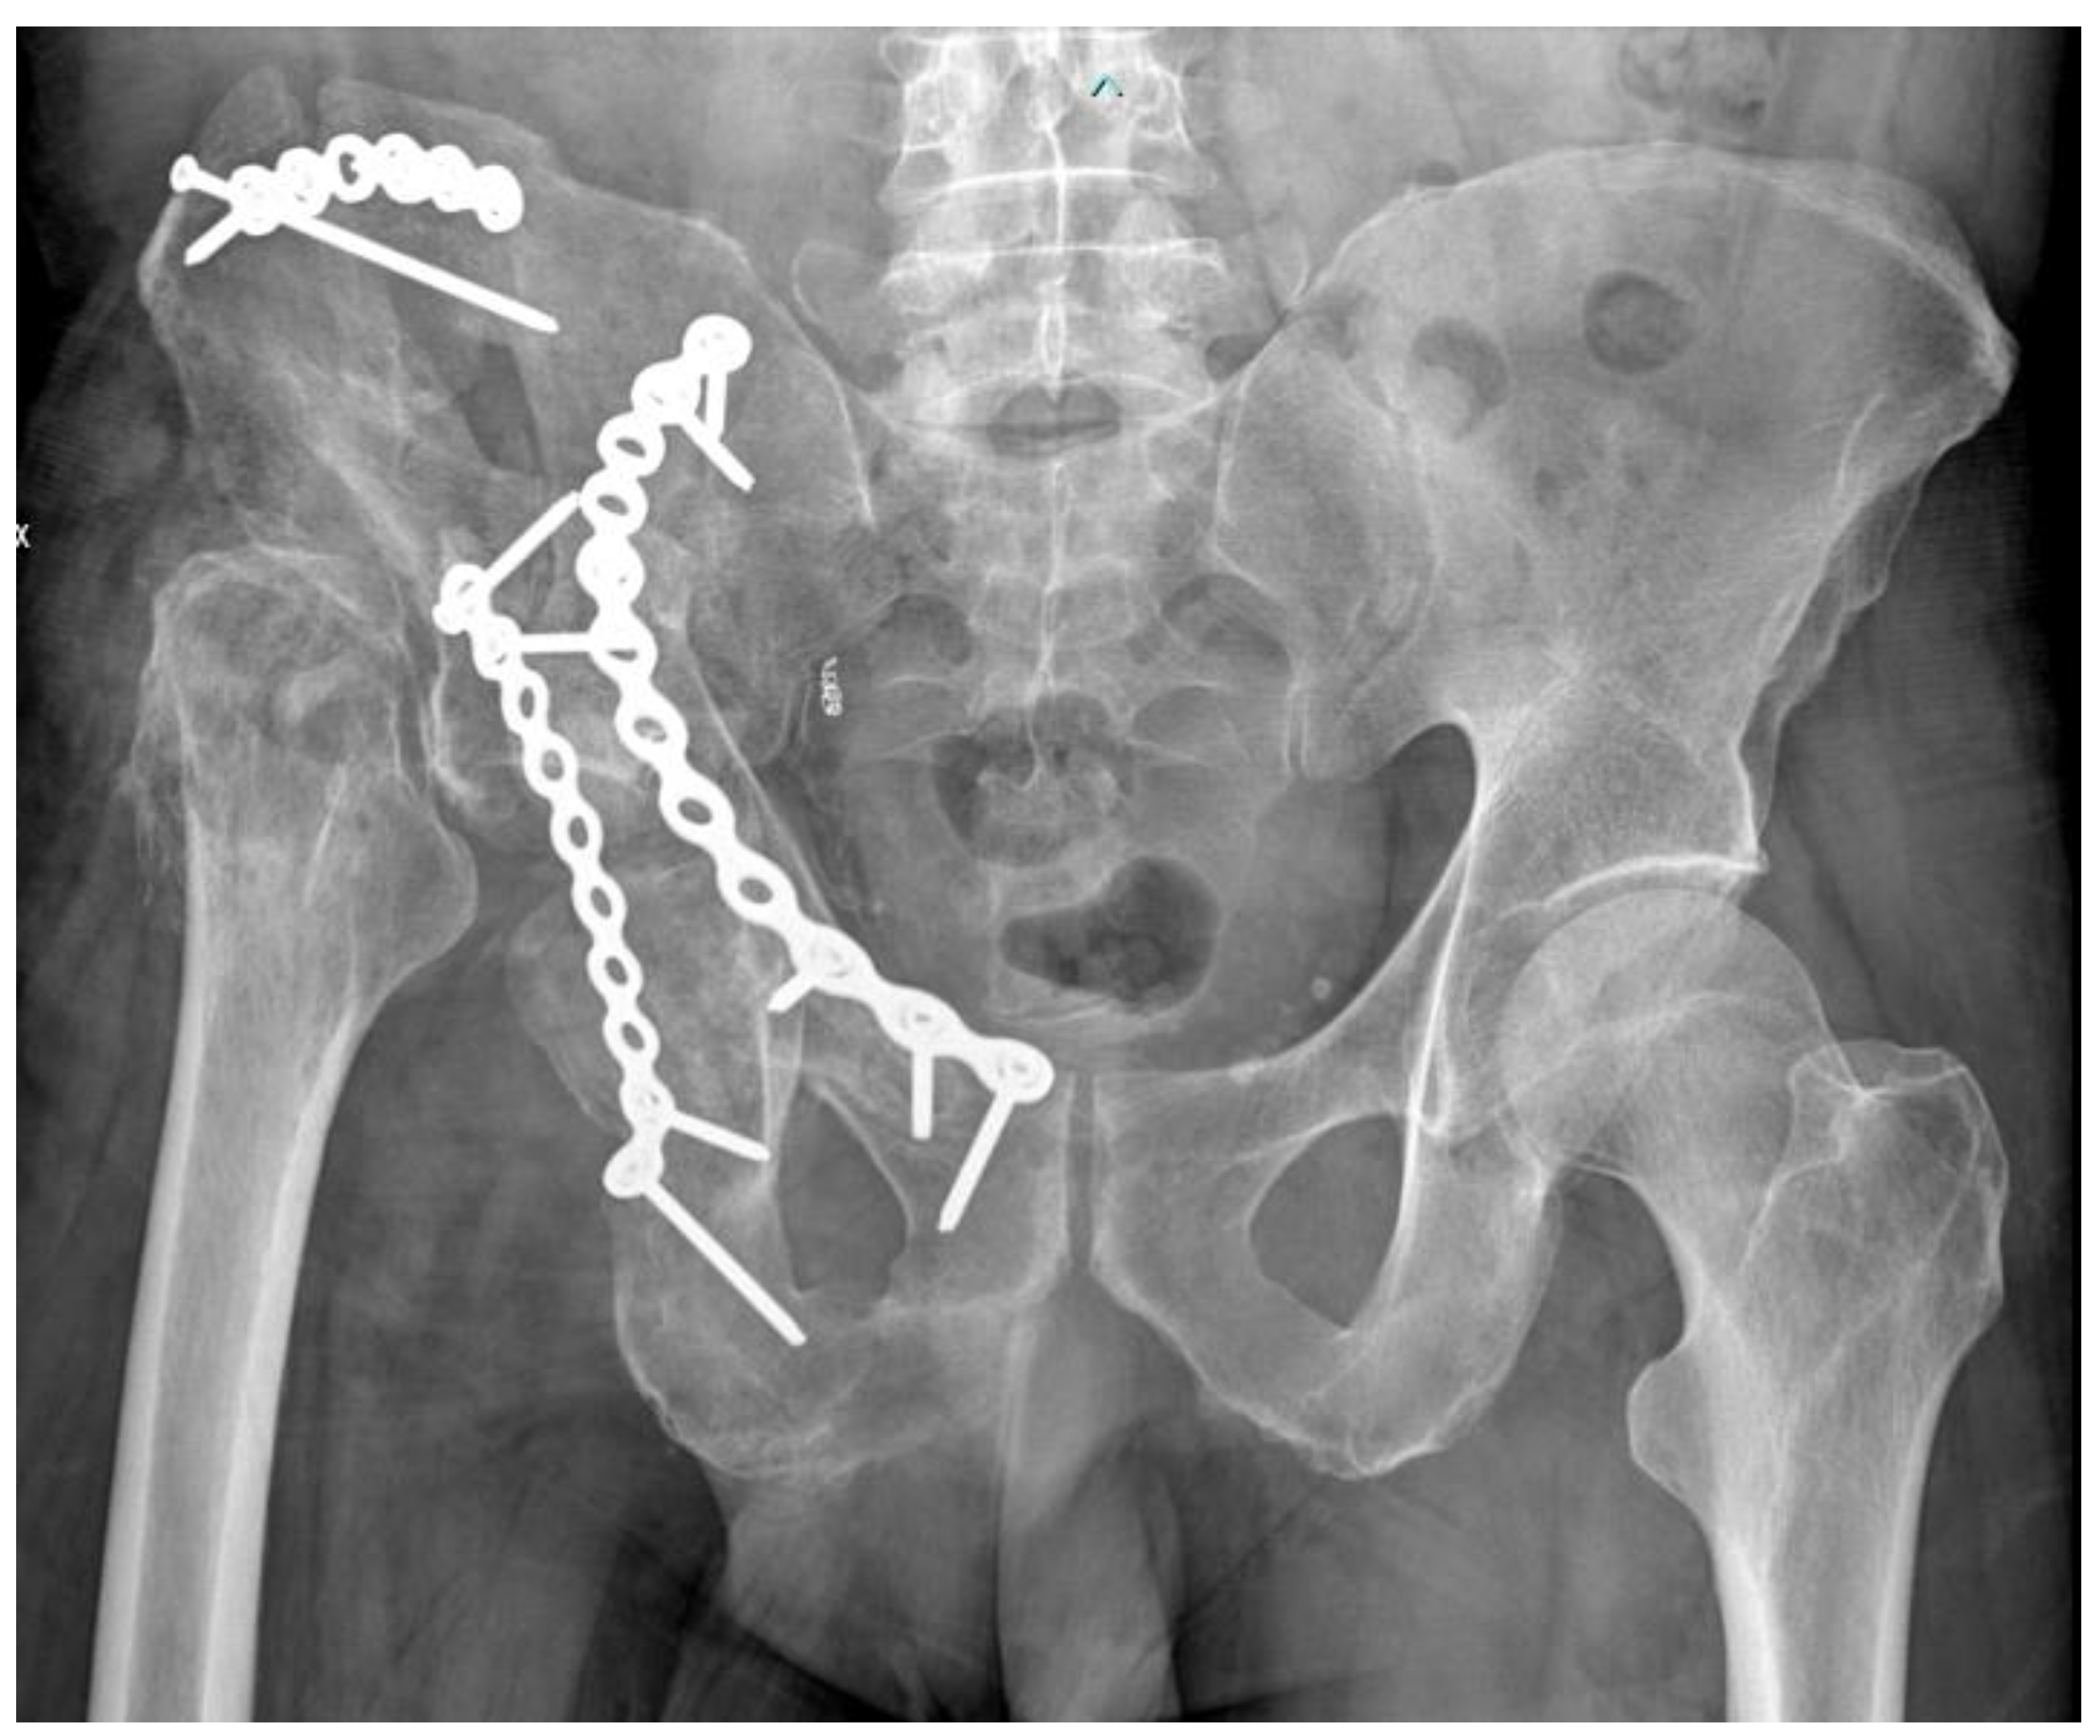

2. Case Report